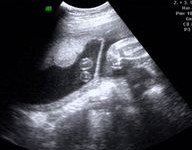

輪狀胎盤超聲診斷

1、輪狀胎盤的特徵性聲像圖改變為胎盤邊緣呈環狀或片狀突向羊膜腔,內部回聲與胎盤實質回聲相似,有出血或梗死者,內部可出現無回聲或低回聲區。

2、探頭對胎盤做放射狀掃查,即對胎盤邊緣做360度搜查觀察,有利於評估輪狀胎盤的程度。如後壁胎盤,由於胎體的影響,可能未能顯示而漏診。